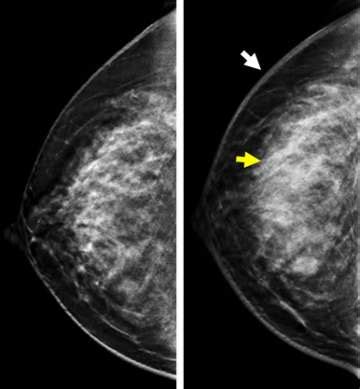

So, why is ultrasound for inflammatory breast cancer such a big deal? Well, traditional mammograms, while excellent for detecting many types of breast cancer, can sometimes miss IBC. This is because IBC often causes diffuse changes throughout the breast, like skin thickening and increased fluid in the breast tissue, rather than a distinct mass. Ultrasound, on the other hand, is fantastic at visualizing these subtle changes. It uses sound waves to create detailed images of the breast’s internal structures. For IBC, an ultrasound can help doctors see:

• Skin Thickening: A hallmark of IBC is thickened skin, and ultrasound is great at measuring and visualizing this.

• Edema (Fluid Buildup): Ultrasound can detect increased fluid in the breast tissue, another common sign of IBC.

Think of it this way: a mammogram is like a general overview, while an ultrasound is like a high-resolution zoom lens that can pick up finer details. This makes it an indispensable tool, especially when a patient presents with symptoms suggestive of IBC. Doctors might order an ultrasound even if a mammogram appears normal, simply because the clinical signs are concerning. The ability of ultrasound to differentiate between solid masses, cysts, and areas of inflammation is also a significant advantage. For IBC, the inflammation and blockage of lymphatics are key features that ultrasound can highlight better than other methods. This detailed imaging allows for a more accurate assessment of the extent of the disease and helps in distinguishing IBC from other conditions that might cause similar-looking symptoms, like benign infections. Ultimately, the goal is to get the most accurate diagnosis as quickly as possible, and ultrasound plays a starring role in achieving that for patients suspected of having inflammatory breast cancer.

Now, let’s get into the nitty-gritty of interpreting inflammatory breast cancer ultrasound results. This is where the radiologist, that specialized doc we just talked about, really earns their stripes. They’re looking for specific patterns and characteristics that are indicative of IBC. As we’ve mentioned, ultrasound for inflammatory breast cancer is key because IBC often presents with diffuse changes rather than a discrete lump. So, what exactly are they scrutinizing on those images?

• Diffuse Parenchymal Enhancement: This refers to increased brightness or signal in the breast tissue on the ultrasound, suggesting inflammation and increased blood flow, which is common in IBC. The radiologist will assess the pattern and extent of this enhancement.

• Skin and Subcutaneous Tissue Thickening: The normal skin thickness is usually just a couple of millimeters. In IBC, this can significantly increase, often exceeding 2-3 mm, and appear irregular. Ultrasound is excellent at precisely measuring this thickness and noting any architectural distortion.

• Edema (Fluid Accumulation): Ultrasound can identify collections of fluid within the breast tissue or in the space between the skin and the breast tissue. This edema is a direct result of the inflammation and blocked lymphatic drainage characteristic of IBC.

• Mammography: This is your standard breast screening tool. It uses X-rays to create images. Mammograms are great at detecting calcifications and distinct masses, which are common in other types of breast cancer. However, with IBC, which often lacks a distinct lump and causes diffuse skin thickening and inflammation, a mammogram might appear normal or show subtle changes that aren’t definitive. So, while it’s often done, it might not be the most sensitive tool for IBC itself.